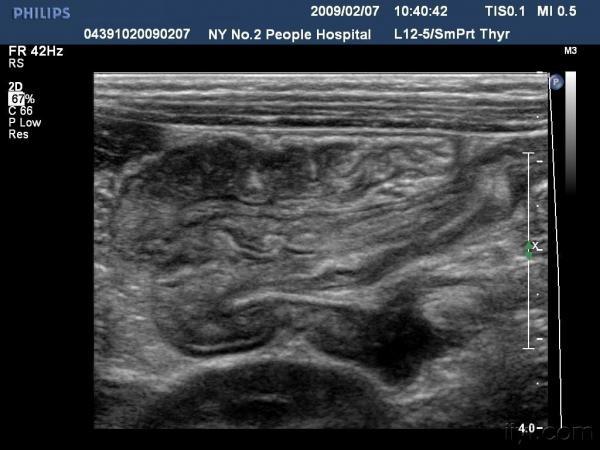

【贴图】肠套叠

患儿哭闹数小时来我院就诊,超声检查发现右侧相当于结肠肝区位置可见“同心圆征”。来和大家分享一下,呵呵。